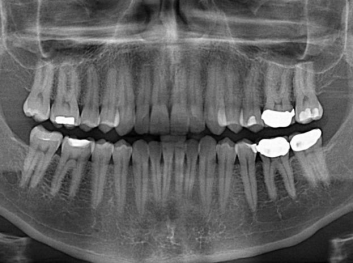

損壞的牙齒如何自我修復(fù)?近日,來自哈佛大學(xué)和諾丁漢大學(xué)的研究人員研發(fā)了能夠刺激牙齒干細胞再生的新型生物材料,而這種新材料研發(fā)成功的背后,正源于他們對牙齒如何實現(xiàn)自我修復(fù)這個課題的不斷探索。

據(jù)美國期刊《大眾科學(xué)(Popular Science)》報道,此種新型生物材料,不僅可以有效地取代傳統(tǒng)補牙填充物,刺激牙齒干細胞再生,患者也有望無需再接受根管治療,使蛀牙患者免除牙根感染或牙髓壞死的苦惱,一個全新的牙齒治療時代即將來臨。

Adam Celiz,是來自諾丁漢大學(xué)的研究人員,他和同事開發(fā)的這種新型合成生物材料,能刺激干細胞在牙髓部的生長。與普通材料一樣,這種合成材料被填充到牙齒并用UV光硬化。

在體外測試中,材料刺激干細胞進入牙本質(zhì)的增殖和分化速度,促進形成牙齒骨組織。研究人員認為,一旦材料在受損牙齒中應(yīng)用,這些干細胞可以自動修復(fù)來自填充物上的損壞。在本質(zhì)上,該生物材料將使牙齒自愈。

在未來,Adam Celiz說,可再生材料能制成各種填充物以便受損牙齒的自身治愈,降低補牙失敗率,甚至?xí)蟛糠秩藢Ω苤委煹男枰?/p>